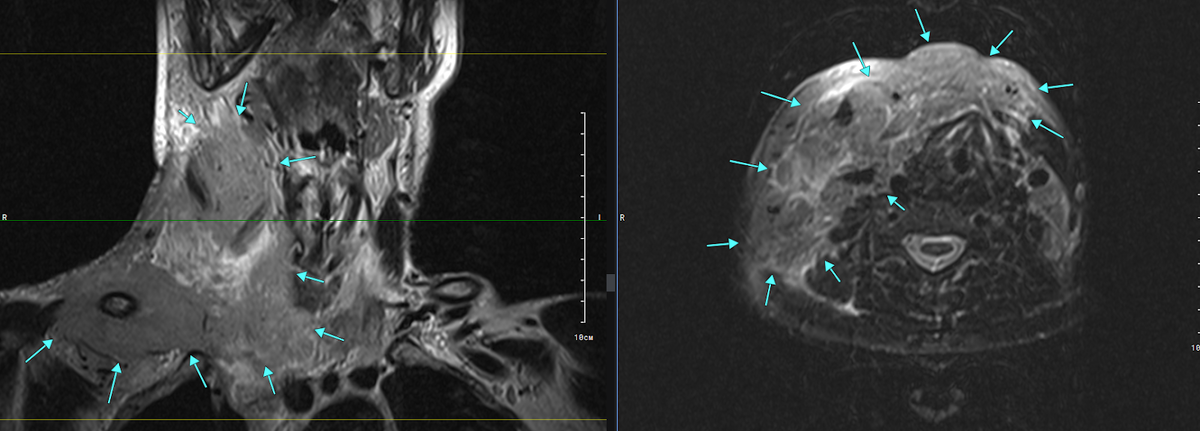

Рис. 1. Т2 корональная плоскость и Т2 FS аксиальная плоскость. Массивный объемный процесс в области передней и правой боковой поверхности шеи [стрелки]

В области передней и правой боковой поверхности шеи, подкожно, межмышечно, а также охватывая в виде муфты все визуализируемые сосудистые структуры и нервные волокна на указанном уровне, а также правую ключицу практически на всем протяжении, тесно прилегая к рукоятки грудины и области грудинно-ключичного сочленения слева - определяется массивное объемное солидное образование.

Данный объемный процесс интимно прилежит практически ко всем отделам щитовидной железы (в меньшей степени - к левой доле), правым и передним отделам гортани, тесно прилежит к правой поднижнечелюстной слюнной железе, правой поверхности гортаноглотки, смещая все вышеперечисленные структуры влево. Также в верхних отделах достигает нижней челюсти справа, в нижних отделах - визуализируется в верхнем средостении, охватывая со всех сторон все сосуды средостения и трахею.